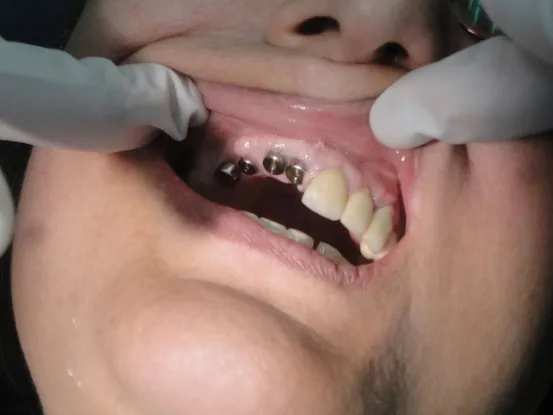

Case 4

58 year old female with unstable partial upper denture due to lack of anchor teeth on upper right quadrant. 4 implants placed and elimination of denture and improved masticatory function.